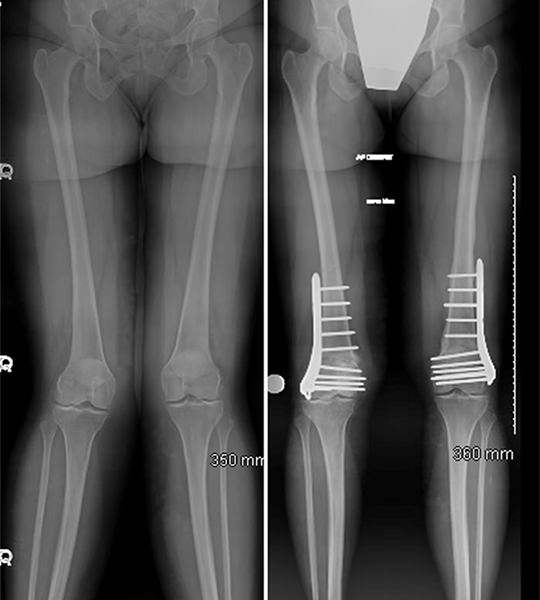

Deformity Correction

Bone and joint deformities can significantly impact mobility, posture, and overall quality of life. Whether caused by birth defects, injury, or improper healing of fractures, deformities require specialized surgical correction to restore natural alignment and improve function. At our center, we use advanced orthopedic techniques to ensure safe, effective, and lasting outcomes.